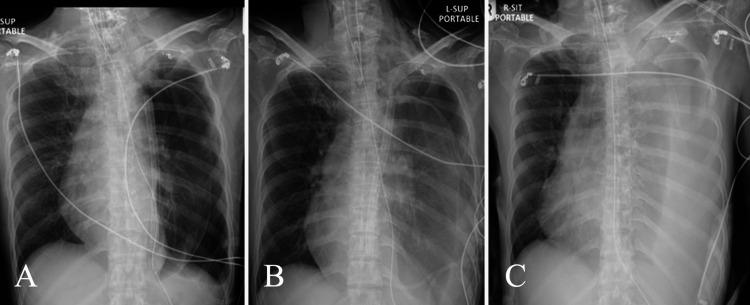

The patient presented with progressive dyspnea. Magnetic resonance imaging revealed a left hemithoracic meningocele arising from the thecal sac at C7-T2. Two attempts at diversion by cystoperitoneal shunts resulted in recurrence. For definitive repair, T2-3 costotransversectomy was performed, and intradural closure of the meningocele opening was performed utilizing spinal dura and autologous fascia lata graft. Trapezius muscle regional flap was turned for reinforcement. Persistent leak warranted reoperation 7 days later. A transthoracic approach was undertaken using video-assisted thoracoscopic resection of the sac at aortic arch level, with reinforcement by latissimus dorsi flap and synthetic materials. Mechanical pleurodesis was performed. Intradural repair of the meningocele opening was revised.

患者表现为进行性呼吸困难。磁共振成像显示在C7 - T2水平的硬脊膜囊出现左侧半胸脊膜膨出。两次尝试通过膀胱腹膜分流术进行分流均导致复发。为进行确定性修复,实施了T2 - 3肋横突切除术,并使用硬脊膜和自体阔筋膜移植对脊膜膨出开口进行硬膜内闭合。翻转斜方肌区域皮瓣进行加固。持续渗漏促使在7天后再次手术。采用经胸入路,在主动脉弓水平通过电视辅助胸腔镜切除囊袋,并用背阔肌皮瓣和合成材料进行加固。实施了机械性胸膜固定术。对脊膜膨出开口的硬膜内修复进行了修正。